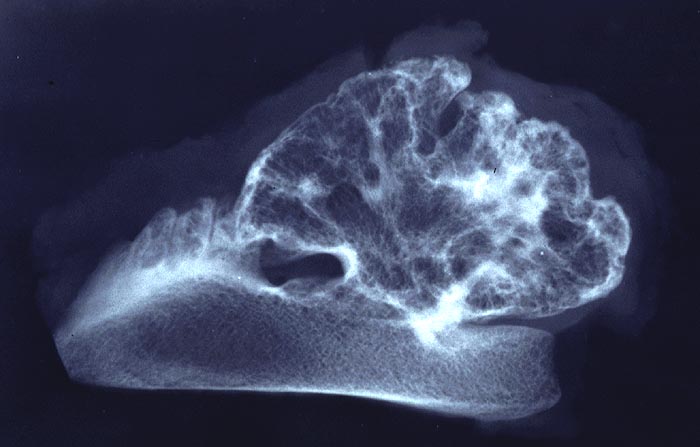

PathoPic – image database / PathoPic ID 5033 - Osteochondrom

Osteochondrom

Knochen, Becken

Präparatradiographie: gestielter exophytischer Tumor mit knolliger Oberflächenkontur. Der knöcherne Stiel stellt sich dar wie normale Spongiosa. Die knorplige Oberfläche ist im Nativ-Röntgenbild nicht abzugrenzen.

Makroskopischer Befund: Auf der Sägeschnittfläche des grösseren Präparates erkennt man scharf abgesetzt vom blutbildenden braunrötlich verfärbten Mark des Beckenkammes einen blumenkohlartig gestalteten Tumor, der in seiner Peripherie eine teils unterbrochene max. 0.3cm dicke Knorpelkappe aufweist. Diese zeigt grauweisse stippchenförmige Verkalkungen.

Exostose Beckenkamm li. DD: Kartilaginäre Exostose.